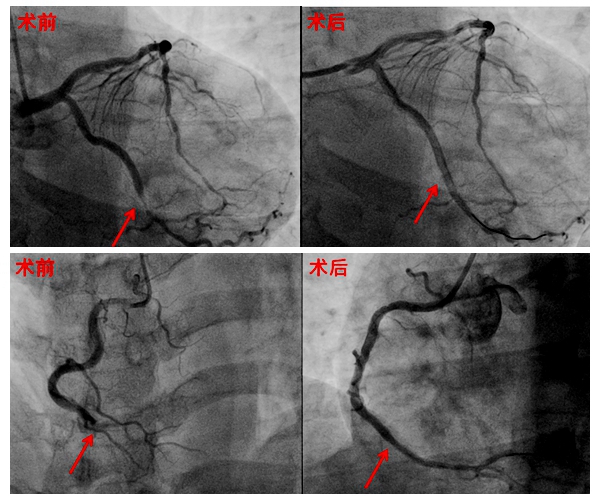

完善冠脉造影示:右冠动脉远段闭塞伴血栓影,回旋支近中段局限性狭窄90%,远段血流减慢。最终在右冠及回旋支病变处分别植入支架一枚,术后支架内未见残留狭窄,远端血流恢复。

术后,患者恢复良好,胸痛未在发作,自觉症状明显改善。